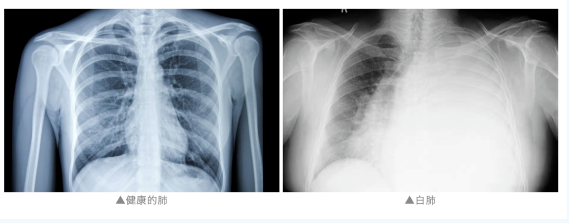

通常来说“白肺”是指急性呼吸窘迫综合征,主要发生在重症感染时,双肺弥漫性病变进展迅速,其症状和严重程度都与支原体肺炎不同。

白肺是一个口语化的描述,指流感导致的并发病毒性肺炎在影像学上呈现为肺部高密度影,看不到正常的肺纹理。这种情况通常表明患者肺里肺炎浸润影的面积超过了75%。白肺患者会出现呼吸困难、低氧血症等症状。流感是一种病毒感染,其症状较一般的普通感冒更为严重,包括鼻塞、流涕、咽痛、咳嗽和发热等。部分患者可能会出现并发病毒性肺炎等病变,在胸部平片或者胸部CT上显示大片白色影像,严重威胁患者的健康。对于流感导致的白肺患者来说,病情会非常严重,需要及时住院治疗,以免延误治疗时机导致病情进一步恶化。